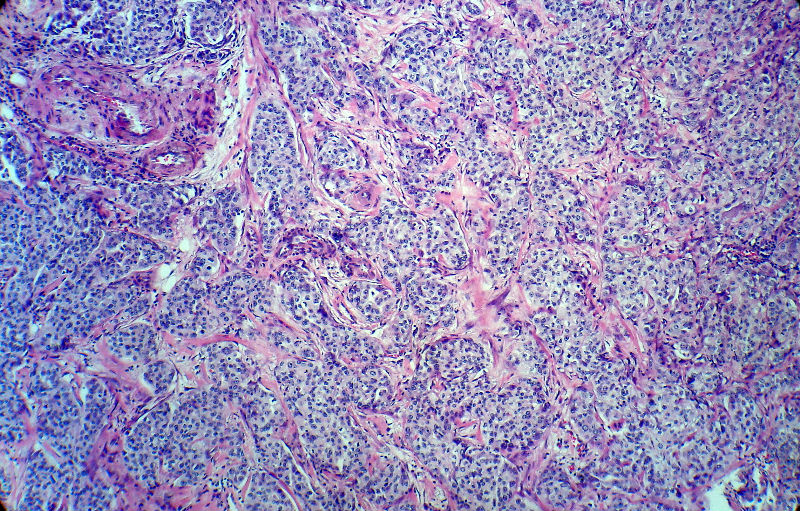

男,82岁,小肠穿孔紧急手术。

大体,小肠一段,长约60厘米,与粘膜面可见三个溃疡型肿物,肠系膜淋巴结肿大。

肿瘤呈巢片状分布,细胞大小相对一致,胞浆丰富,胞核呈细颗粒状,可见小核仁,血管较丰富,考虑神经内分泌肿瘤,加做免疫组化(Ki67、Syn、NSE、CgA、CD56)分级。